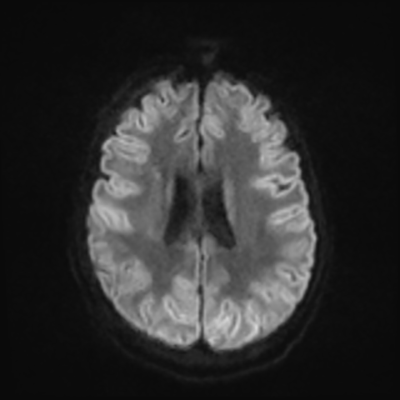

MRI brain (DWI)

You can clearly see diffuse cortical and basal ganglia diffusion restriction, and that of his deep cerebellar nuclei as well. The right occipital lobe abnormalities are a little more prominent, but then you remember that he is known to have had a right occipital stroke weeks ago.